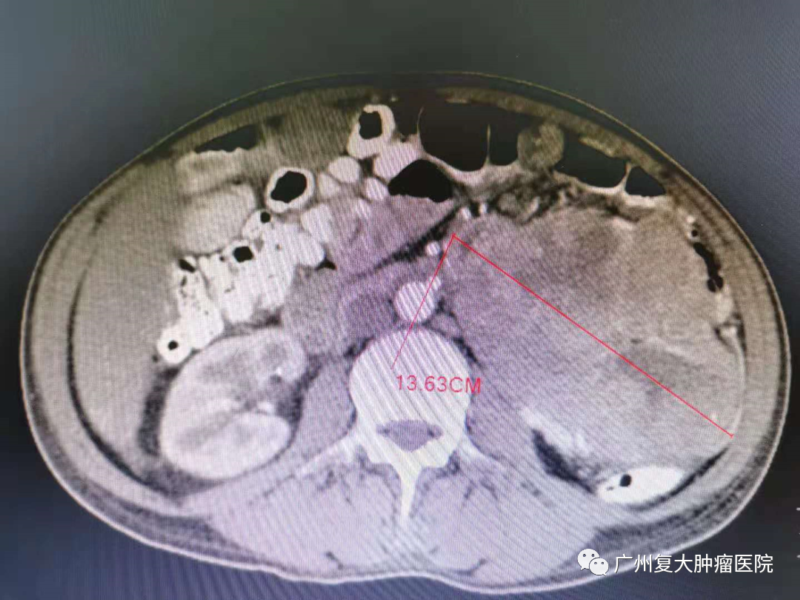

肝肿瘤前后对比,肿瘤缩小,肿瘤细胞基本坏死;

肠肿瘤前后对比,肿瘤缩小,肿瘤细胞基本坏死

经过了几次介入治疗后,陈先生整个人精神了很多。值得高兴的是,他的影像资料显示肝脏与肠的肿瘤有所缩小,医生告诉他肿瘤基本坏死,降低生命的危险性。“我现在坐着躺着睡都没事,不像以前躺着肩膀痛,气还上不来出不去。”结束完此次治疗后,陈先生将回家休养,谨遵医嘱,提高自己的身体素质,他也期待下一次的复查结果。